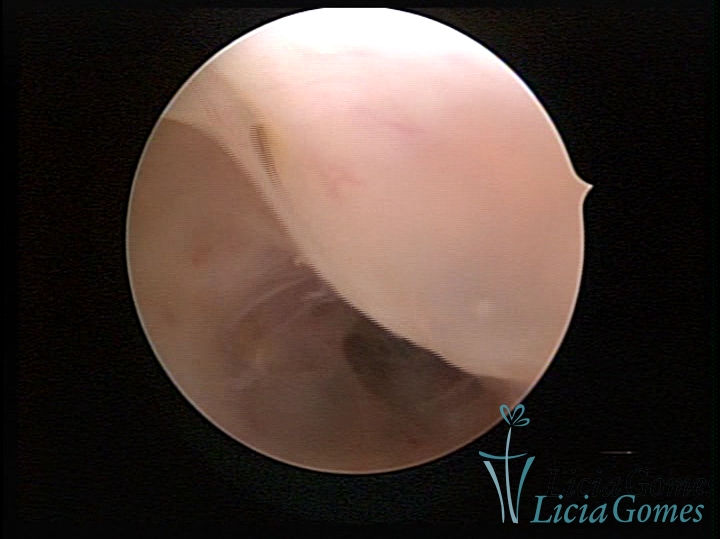

FIBROUS SYNECHIA

Uterine synechiae are scars (adherence) between the surface of the uterine walls, which may occur after the surgical procedure, uterine curettage, or after an inflammatory process in the uterine cavity (endometritis), which may lead to menstrual changes, infertility and obstetric complication such as abortion and premature birth.